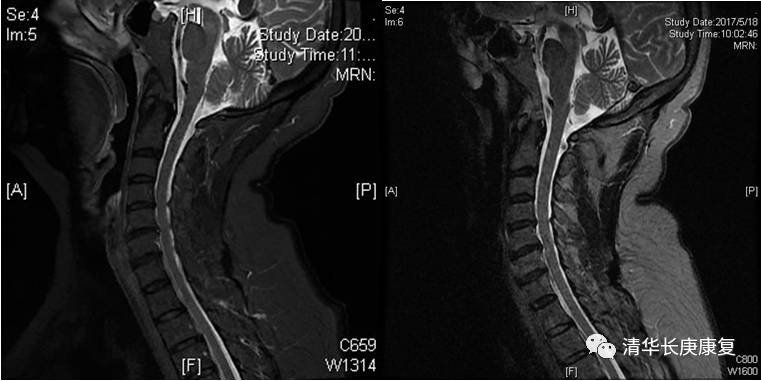

研究表明,运动治疗能很好地改善胸椎后凸的问题,从而不仅能缓解颈椎病的疼痛,同时也能达到纠正颈椎曲度的效果,从而减轻颈椎的压力。患者李女士,60岁,患有腰椎滑脱伴左下肢疼痛3年,右侧膝关节关节镜术后2月,同时伴有驼背,颈髓压迫,导致双侧上肢麻木、疼痛。在强化治疗腰椎的基础上,同时强化胸椎的治疗,在对颈椎不进行过大活动的情况下,经过三个月的治疗,改善了腰椎的症状,同时调整了颈椎的曲度,缓解颈髓受压情况,同时也为躯干整体的核心稳定达到了一个良好的基础,对腰椎和下肢的治疗提供了很好的基础。

患者训练前后MRI对比